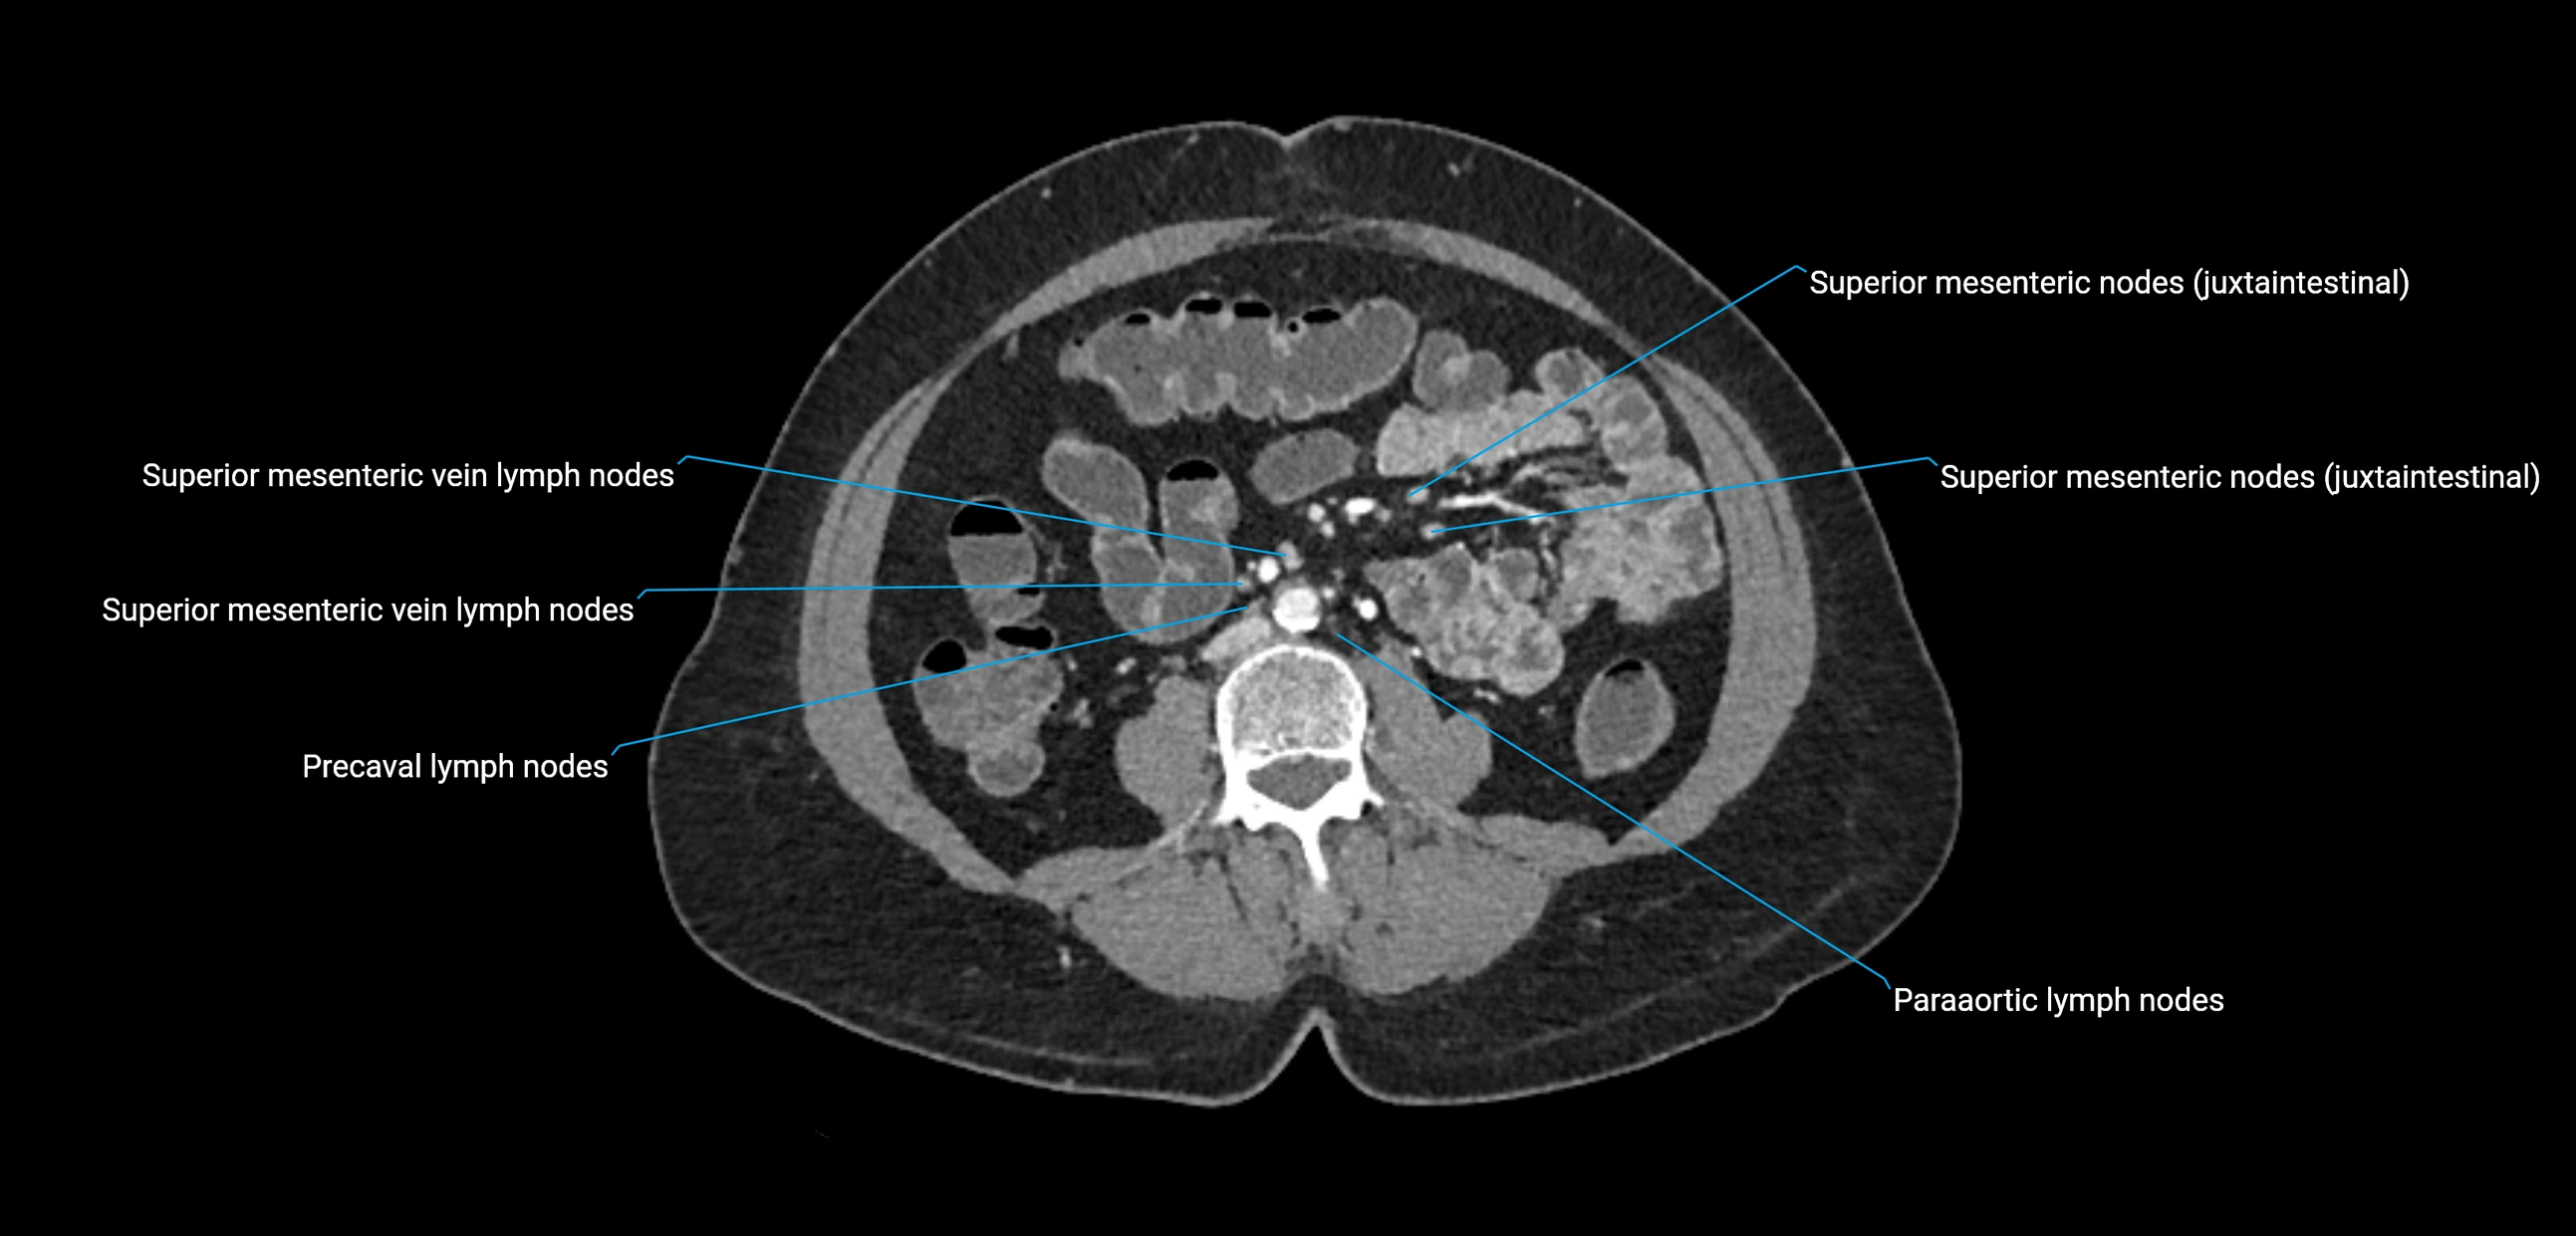

MRI images

image